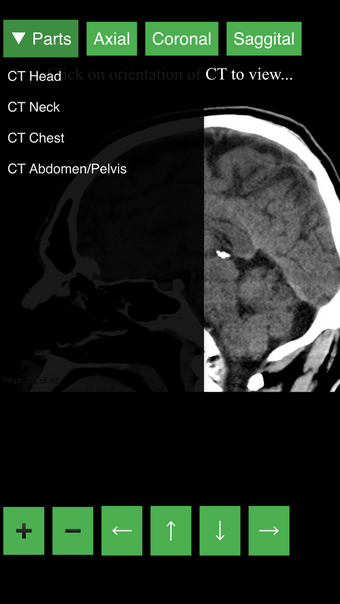

Radiology CT Viewer - полезный инструмент для врачей, медицинских студентов, радиологических техников и других медицинских специалистов, которые хотят узнать больше о человеческом теле и его анатомии. Приложение содержит подробные сечения наиболее важных частей тела. Кроме того, оно содержит интерактивную 3D-модель, которая позволяет вращать, увеличивать и перемещать камеру вокруг изображения, чтобы получить лучший обзор анатомии.

Если вы ищете инструмент, который поможет вам узнать больше о человеческом теле, Radiology CT Viewer - отличный выбор. Он содержит подробные иллюстрации и интерактивную 3D-модель.